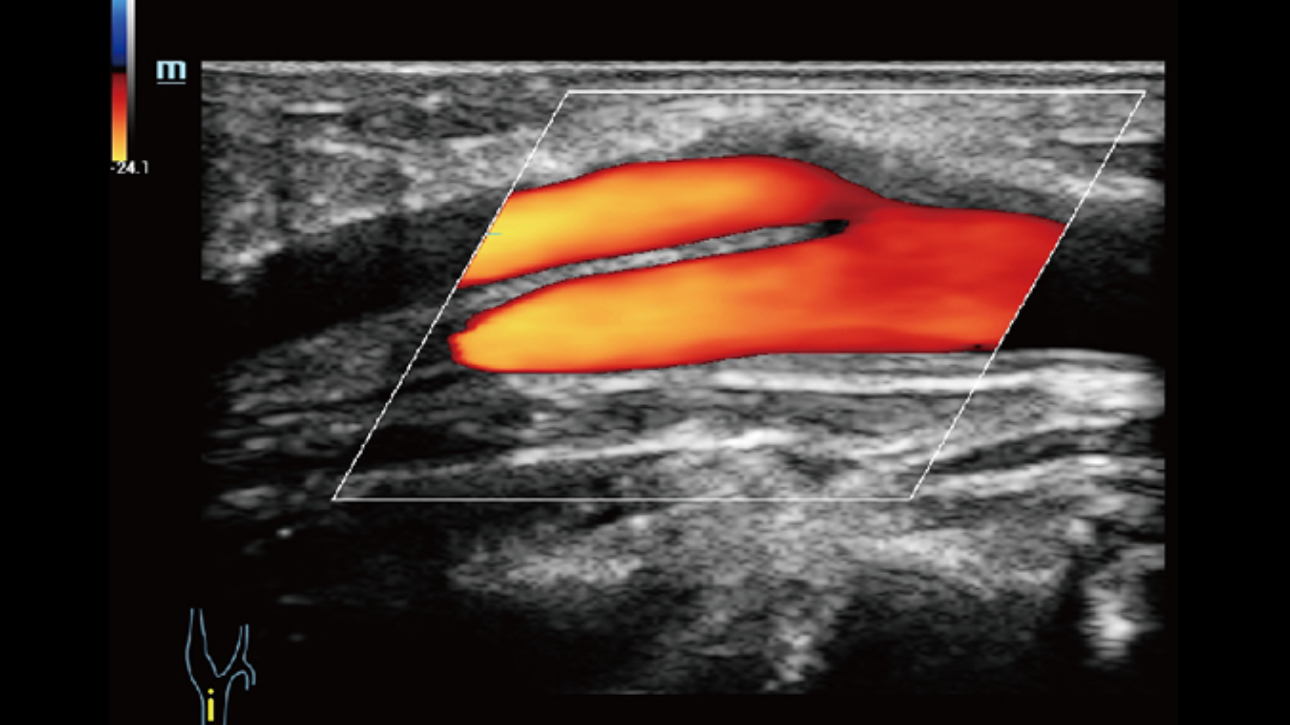

Dynamic Pixel Focusing technology allows the Resona 6 to achieve extreme uniformity in pixel level throughout the whole field of view. Now there's no need to adjust the focal positions to achieve uniformity across patient exams.

By retrospectively analyzing complete channel data stored in channel data memory, the Resona 6 is able to intelligently choose the optimal sound speed to improve image accuracy even with tissue variation, allowing for adaptive tissue-specific optimization.

Channel data based ZST+ provides Enhanced Channel Data Processing for greatly improved imaging clarity. By multiple and retrospective channel data processing, it makes the best use of acoustic information for image improvement.